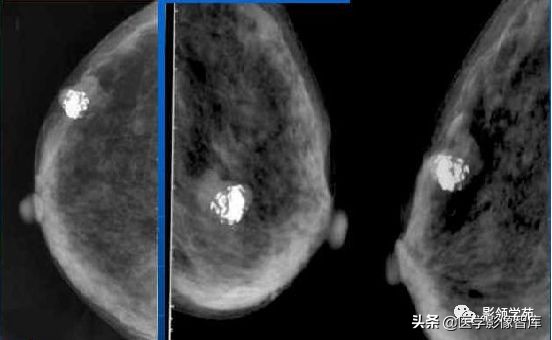

4. Coarse or 'Popcorn-like'

纤维腺瘤(fibroadenoma):典型的粗大爆米花样钙化。有时在肿瘤包膜边缘形成钙化,表现为环状钙化。与恶性钙化相比,纤维腺瘤的钙化通常较粗大于 2 mm, 分布更趋向边缘。

成簇分布,左乳退化型纤维腺瘤:

钙化略小且较密集,注意与恶性钙化鉴别。